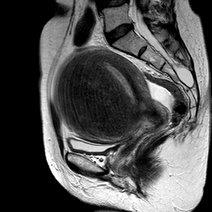

[最佳答案] 腺肌瘤一般是指子宫腺肌症,患者会出现痛经、月经量增多等月经失调症状,对女性生育功能影响比较大,可能会导致不孕症,需要针对不同情况采取治疗方法。腺肌瘤是一种由于黏膜层组织异位到子宫肌层,而产生的一种瘤样良性疾病,近年来由于剖宫产、流产率上升,此疾病的发生率也有逐年上升趋势,临床上多采用药物治疗、手术治疗、期待治疗等。 1、期待治疗:指的是无需进行治疗,定期进行检查腺肌瘤的生长,观察病情进展情况,常适合临近绝经的患者; 2、药物治疗:常用的药物有桂枝茯苓胶囊、宫瘤消胶囊、逍遥丸等中成药,但起效较慢,可能效果并不明显,主要针对较小的子宫肌瘤。也可以服用抗宫炎片或激素类药物,如戈舍瑞林、亮丙瑞林、米非司酮等抑制子宫肌瘤生长,但不可擅自服用,还可以进行局部药物治疗,如促性腺激素抑制激素或左快诺孕酮宫内缓释系统治疗,建议在医生指导下结合个人情况选择药物; 3、手术治疗:建议定期到医院复查,密切观察肌瘤的生长情况,如果肌瘤生长过快,需要采用手术治疗。根据个人情况采取根治性全子宫切除术、子宫腺肌瘤切除、子宫肌层电凝术、子宫内膜及肌层切除术、子宫动脉阻断术等手术方式,其中全子宫切除术适用于无生育要求的患